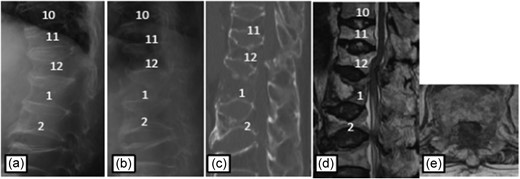

Case 3

Plain radiographs on initial assessment (a) and on admission (b); Sagittal CT image (c) showing the hyperextension fracture at L1 and dislocation of it; MRI T2-weighted image (d, e) showing the severely compressed spinal cord at T12 level.